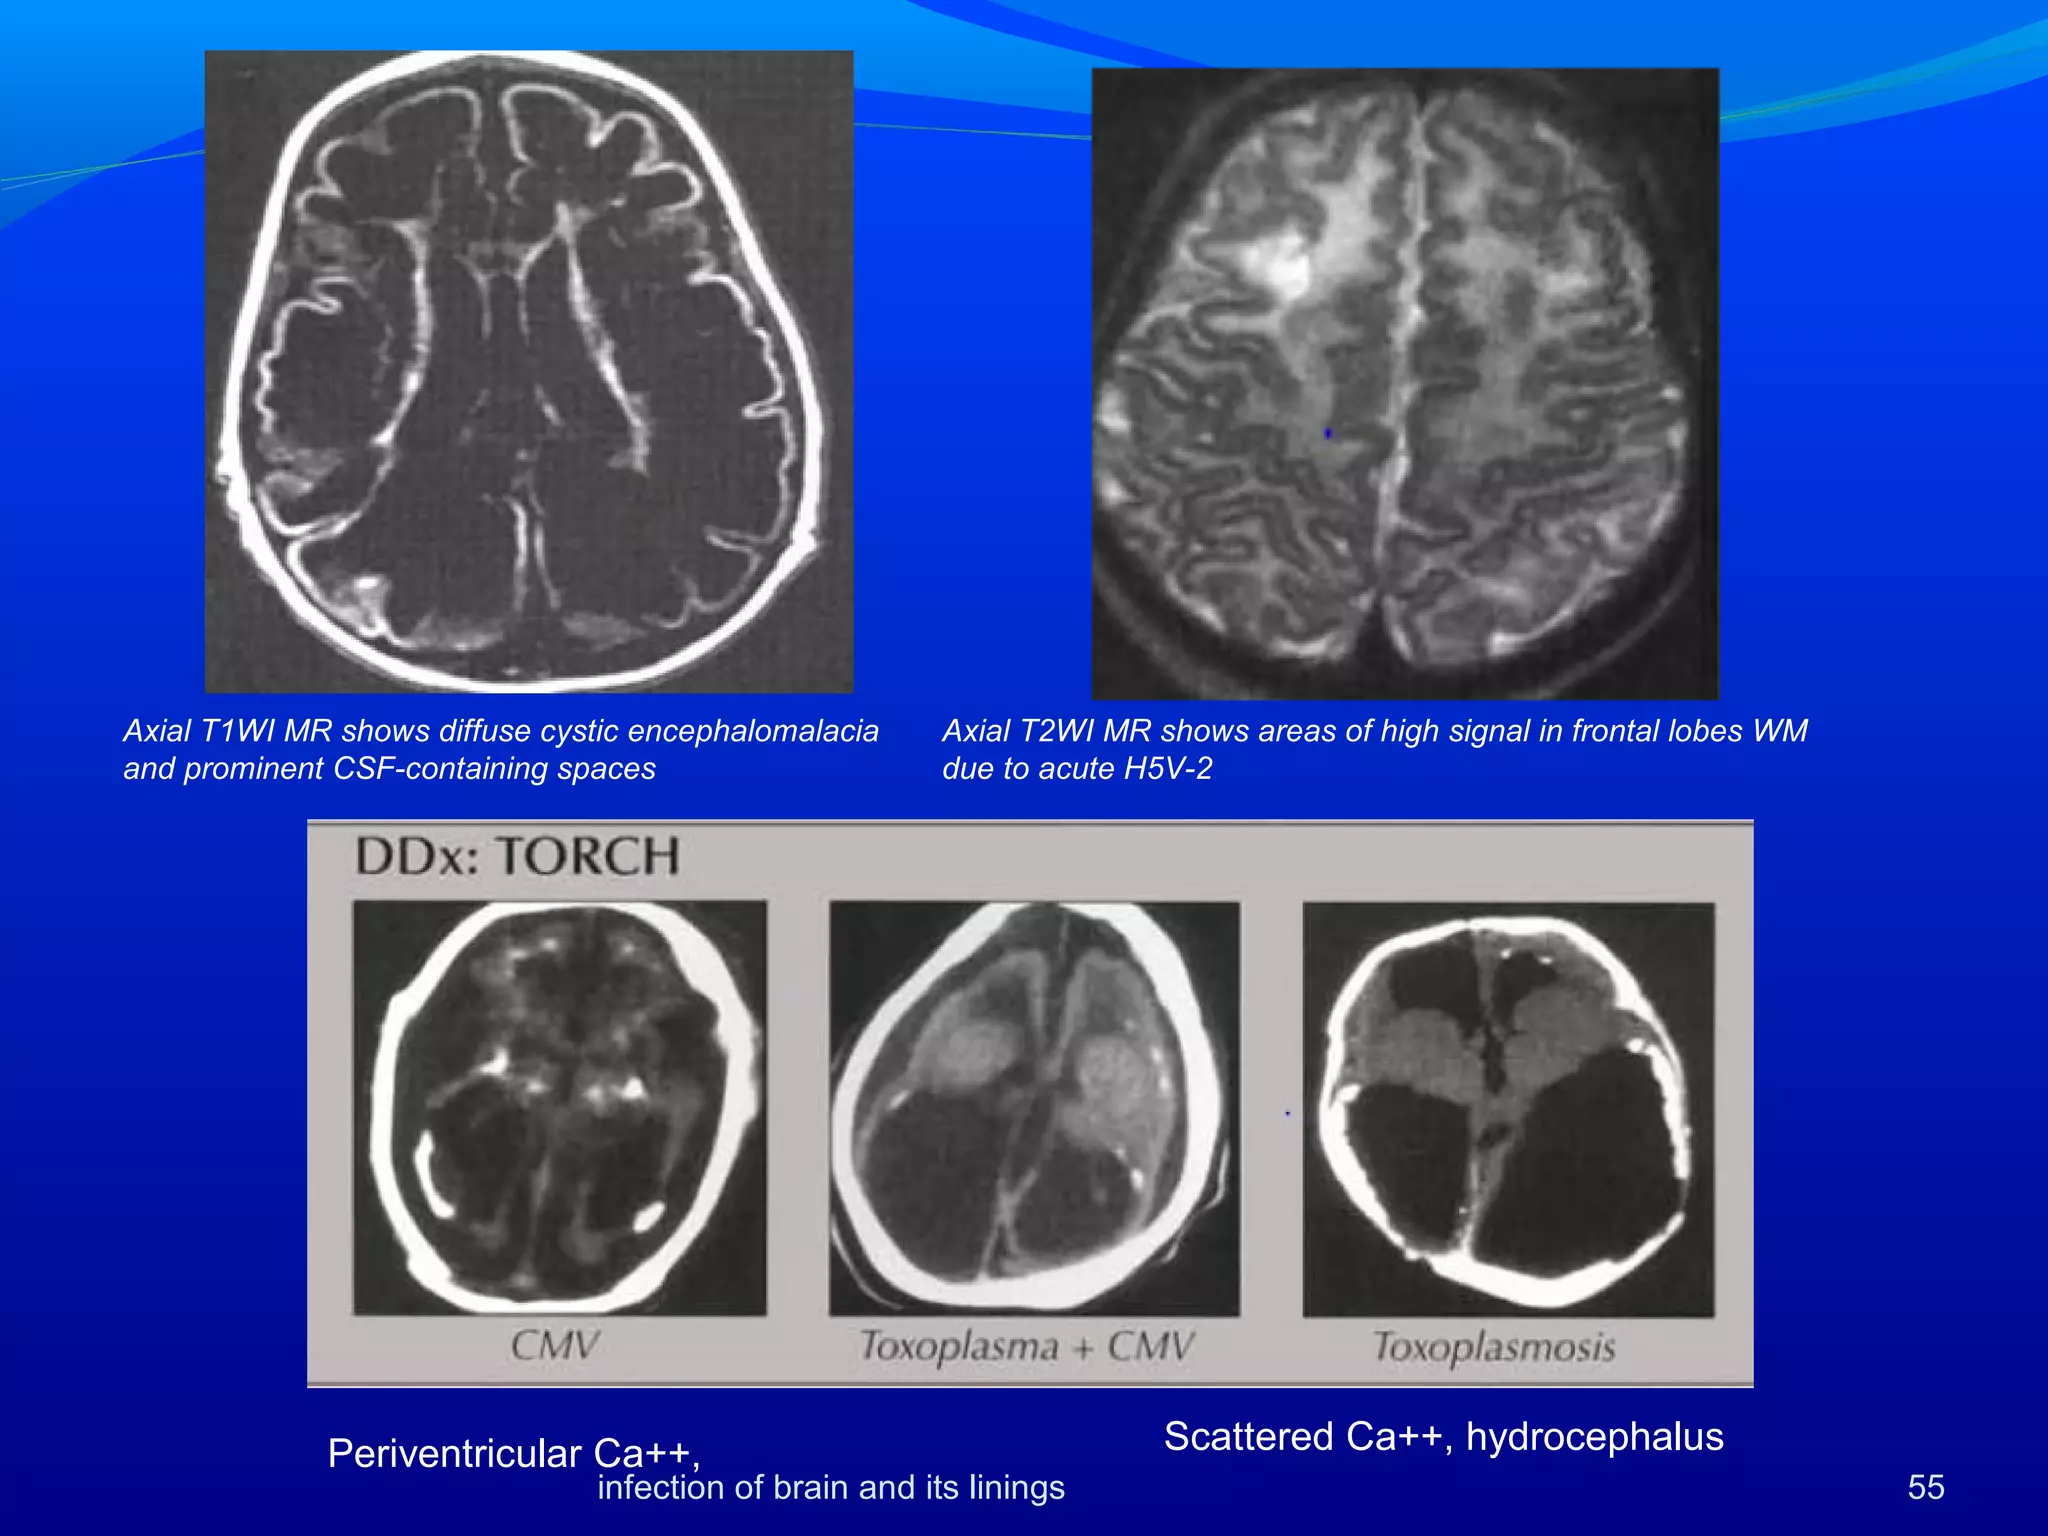

HSV 2

Both HSV1 and 2 are commonly prevalent in Indian

population. (Mixed=83%, HSV1=10%, HSV2=1%) [1]

HSV2 along with TORCH agents are major causes of

neonatal encephalitis.

Infections result from maternal birth canal or

transplacental spread

Unlike HSV1, HSV2 infection in neonates is

diffuse.

1.Shivaswami 2005. IJDVL 71:26

Imaging findings are nonspecific.

CT scans in early disease may be negative or show

subtle areas of low density

. Conventional MR and DWI show lesions better.

 Lesions may be multifocal involving almost any area of

brain or limited to temporal lobes brainstem and

cerebellum.

Watershed infarcts may be seen [1]

 In-utero infections can result in microcephaly,

encephalomalacia or calcification.

1)Vossough.2008. Neuroradiol 50:355

Axial T2WI MR shows areas of high signal in frontal lobes WM

due to acute H5V-2

Axial T1WI MR shows diffuse cystic encephalomalacia

and prominent CSF-containing spaces

Scattered Ca++, hydrocephalusPeriventricular Ca++,

55infection of brain and its linings